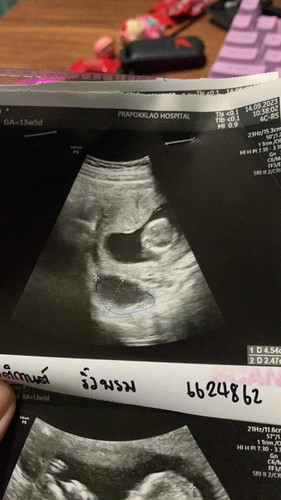

ไปตรวจเจอน้องแล้วค่ะ13วีค แต่คุณหมอบอกว่าเจอซีส จะเป็นอันตรายไหมคะ #ขอบคุณสำหรับคำตอบค่ะ #ท้องแรกคะ